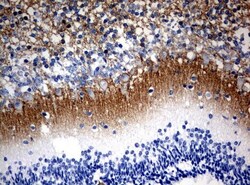

- Submitted by

- Invitrogen Antibodies (provider)

- Main image

- Experimental details

- Immunohistochemical staining of paraffin-embedded human embryonic cerebellum using anti-VSNL1 mouse monoclonal antibody. (UM800034; heat-induced epitope retrieval by 10mM citric buffer, pH6.0, 120°C for 3min)